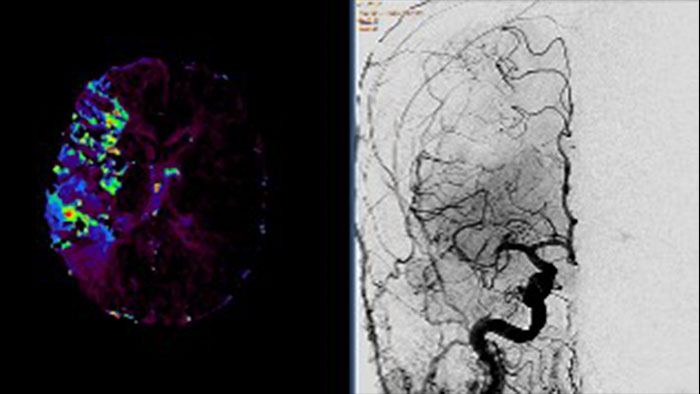

Vascular Processing - DSA (in MMV)

XA Vascular Processing - DSA (in MMV)

Contrast arterial structures with surrounding bone and soft tissue to assist in identification of vascular abnormalities

The XA Vascular Processing – DSA (in MMV) expands your workflow by allowing you to read and post-process iXR images virtually anywhere. Obtain images of arteries in various parts of the body using tools to perform standard and run subtractions, pixel shifting, and landmarking. This application also provides post-processing tools to edit and optimize the DSA XA data created in the interventional room.

vascular processing thumbnail

Benefits

• Single image and ‘Run’ subtraction.

• Pixel Shifting to correct for patient movement during contrast injection and can be performed manually.

• Landmarking helps set a partial subtraction factor.

• Partial subtracted image shows (to a certain degree) the complete image, with the contrast enhanced depending on the subtraction factor.

• Same workflow as in the Philips Allura system.